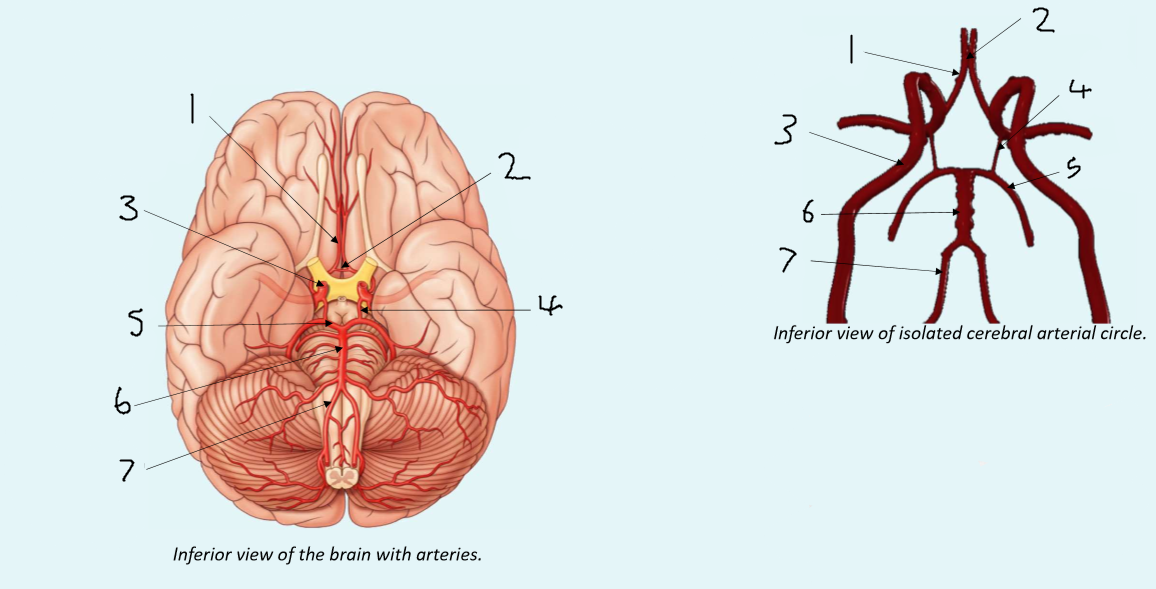

What is 1?

anterior cerebral artery

What is 2?

anterior communicating artery

What is 3?

internal carotid artery

What is 4?

posterior communicating artery

What is 5?

posterior cerebral artery

What is 6?

basilar artery

What is 7?

vertebral artery

What is 1?

anterior communicating artery

What is 2?

anterior cerebral artery

What is 3?

middle cerebral artery

What is 4?

internal carotid artery

What is 5?

posterior communicating artery

What is 6?

posterior cerebral artery

What is 7?

superior cerebellar artery